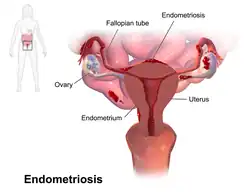

Endometriosis

Endometriosis is a disease in which tissue similar to the endometrium, the lining of the uterus, grows in other places in the body outside the uterus.[8][9] It occurs in humans and a limited number of other menstruating mammals. Endometrial tissue most often grows on or around reproductive organs such as the ovaries and fallopian tubes, on the outside surface of the uterus, or the tissues surrounding the uterus and the ovaries (peritoneum).[3] It can also grow on other organs in the pelvic region like the bowels, stomach, bladder, or the cervix.[10] Rarely, it can also occur in other parts of the body.[3]

Most often, endometriosis is found on the:

- Ovaries

- Fallopian tubes

- Tissues that hold the uterus in place (ligaments)

- Outer surface of the uterus[3]